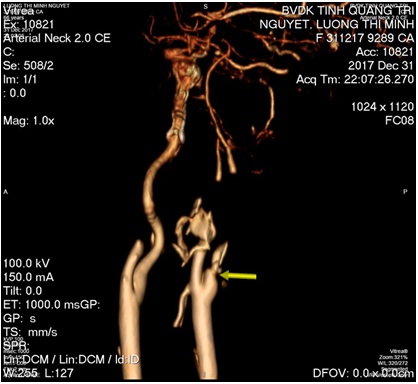

+ MSCT mạch máu não: Tắc hoàn toàn động mạch cảnh trong bên trái.

Hình: ĐM cảnh trong trái trước và sau lấy huyết khối (còn tắc M1 trái)